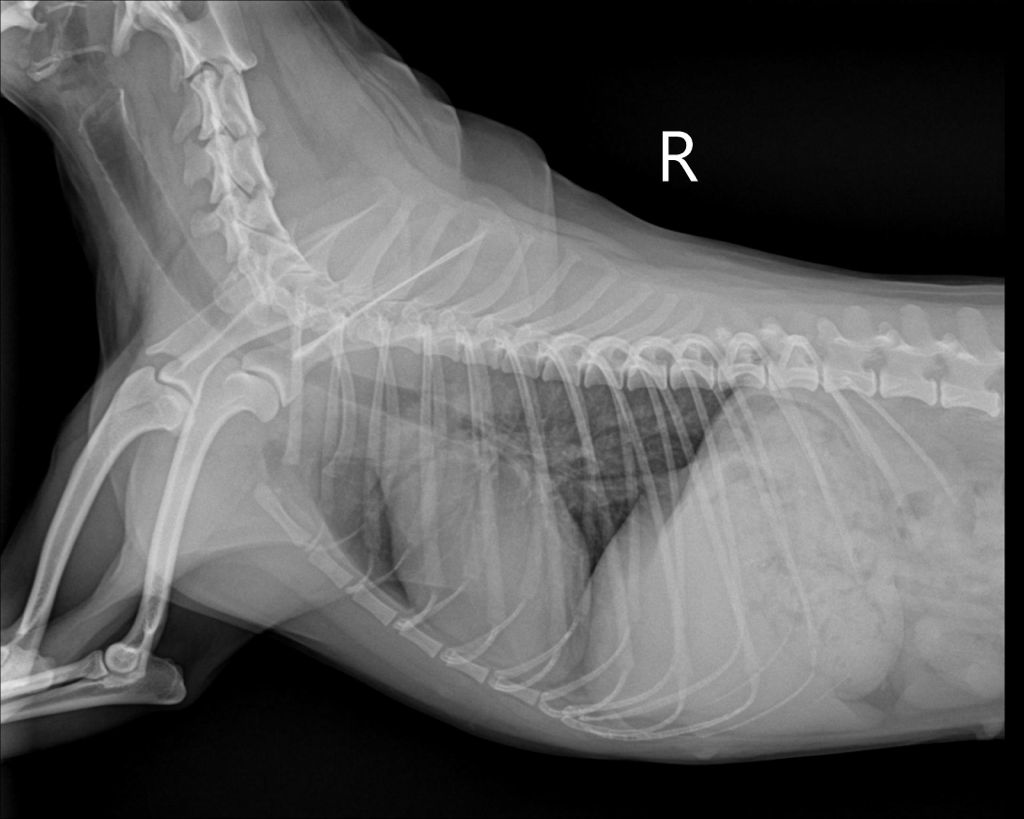

우리 강아지 디스크 일까요..?움직이지 않아요

평소랑 달리 움직이없고 헥헥 거리며 끙끙 앓아요 사진상으로 디스크 의심갈만한 문제가 없어보인다는데 전문가들의 의견이 궁금합니다 ㅜ ㅜ

방사선 만으로는 디스크를 확진할 수 없습니다.

그외 신경검사인 심부통증 반응과 자세반응 등 신경계 검사와 확진을 위해서는 CT촬영과 MRI 촬영이 필요합니다.

화살표를 해둔 부분의 디스크 공간이 좁아 보이는 양상이 경미하게 관찰되어 의심해볼만한 가능성은 있으나 디스크는 엑스레이 사진으로 진단되는 질환이 아니기에 다른 검사 결과에서 디스크를 강력히 의심할만하다면 MRI 검사가 추천됩니다.

반복된 촬영에서 재현성도 확보되어 증상이 지속된다면 이 사진을 근거로 MRI 촬영을 해봐야 하는 사항으로 판단됩니다.